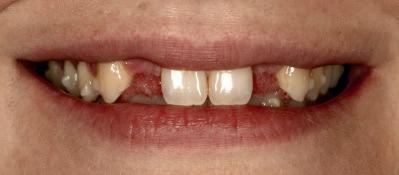

In the UK, dental care and oral health services have been marginalised for decades, despite clear evidence of need and persistent calls for reform. Successive Secretaries of State for Health deferred decision-making, kicking the dental can down the road. This institutionalised apathy has led to stark disparities with entire regions of England, termed “dental deserts,” where accessing affordable dental care is impossible. Many local authorities have also neglected their oral health promotion responsibilities. The consequences are devastating. Childhood tooth decay remains the leading cause of hospital admissions, despite being almost entirely preventable.

Adults face insurmountable barriers to care, some resorting to DIY dentistry or forgoing treatment altogether. The insidious second order effects on systemic health multiply, for the patient and the public purse.